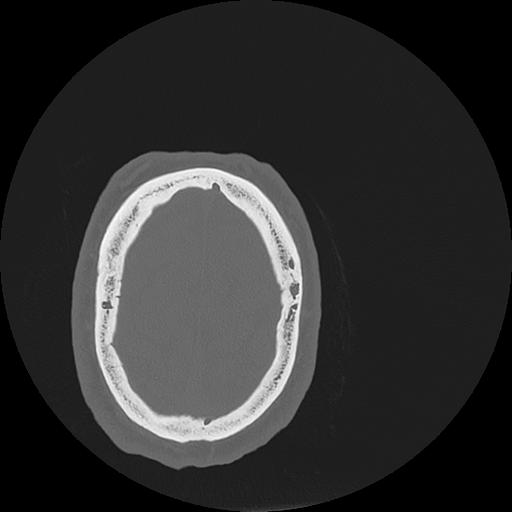

7 HUESO,,Vol,0.5,HUESO,,